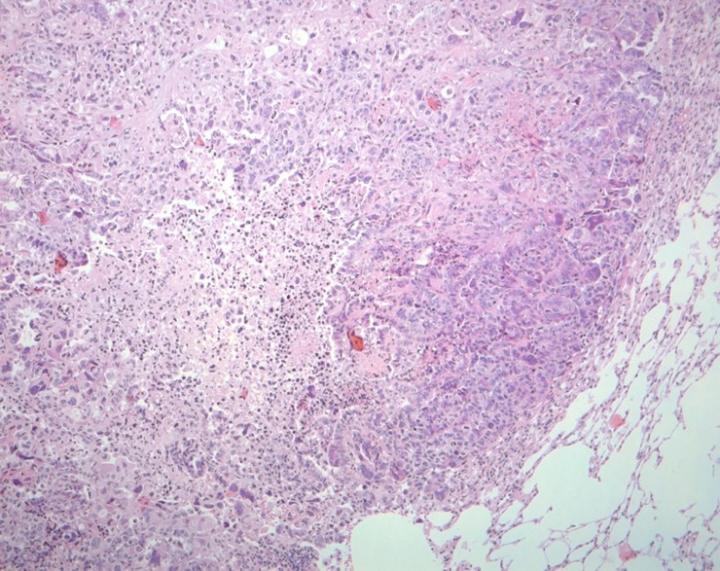

Lung cancer is one of the most prevalent types of cancer, with more than 20,000 new cases diagnosed each year in Spain. Lung adenocarcinomas carrying oncogenic KRAS , the engine driving these tumours in 30% of cases, constitute the most aggressive sub-type because, unlike other types of lung cancer, there are no targeted therapies beyond the standard cisplatin-based treatment.

Researchers of the Experimental Oncology Group at the Spanish National Cancer Research Centre (CNIO), headed by Mariano Barbacid, director of the Group, and the researcher David Santamaría, will be publishing a paper in the prestigious journal Nature Medicine this week explaining how the combination of dasatinib -- DDR1 protein inhibitor -- and demcizumab -- a Notch pathway inhibitor antibody -- specifically and effectively reduces lung adenocarcinomas and improves prognosis and survival rates substantially. Once the preclinical studies have been completed, "the next step in this research would be the clinical trials to validate the combination of these drugs as the first therapy directed against these aggressive tumours," says Chiara Ambrogio, first author of the paper.

The authors of the paper have used preclinical models of genetically modified mice. In collaboration with the team of Alberto Villanueva in the Catalan Institute of Oncology (ICO), they generated orthotopic mouse models by implanting lung tumours from patients in order to validate the effectiveness of the drugs directly on human samples. The teams of Manuel Serrano and Manuel Hidalgo from the CNIO have also participated in the study.